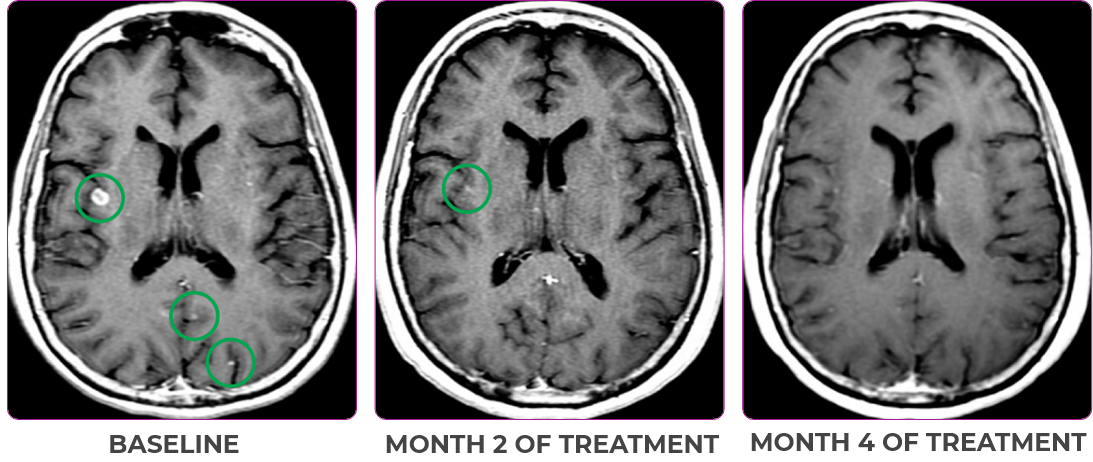

Response in primary and metastatic lesions1

MRIa imagery of the brain. Green circles indicate baseline brain metastases.1

SCAN 2: BRAIN

aMRI, magnetic resonance imaging.

MRIa imagery of the brain. Green voxels indicate decreased burden of metastatic disease; further quantified by accompanying measurement in green.1

SCAN 3: BRAIN

Pre- and post-treatment imaging, by Rosen EY et al, is licensed under Creative Commons License CC BY 4.0.

- Partial response to treatment that was confirmed at 2 months (34% tumor reduction)

- Grade 1 cough and Grade 2 fatigue

- Patient remains on VITRAKVI after more than 4 months of treatment

aBID, twice daily; NSCLC, non-small cell lung cancer; PR, partial response.